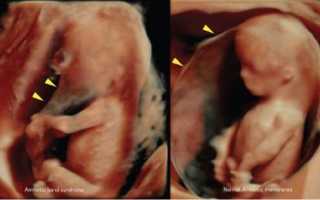

Диагностика

Обнаружить тяжи в амниотической жидкости можно с помощью ультразвукового исследования, которое проводится в начале второго триместра, хотя это не всегда удается. Нити могут быть настолько тонкими, что их сложно заметить на экране. Если у ребенка впоследствии будут выявлены деформации частей тела, то устанавливается соответствующий диагноз.

Если потребуется провести дополнительные исследования, то может быть назначено 3D-УЗИ, МРТ и эхокардиография плода. Эти процедуры необходимы для предотвращения серьезных последствий для здоровья малыша.